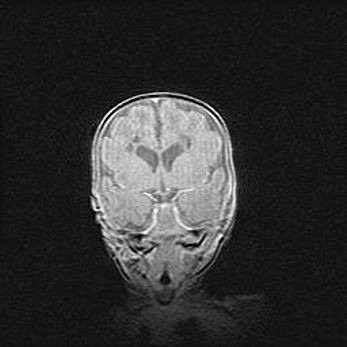

Церебральная ишемия II.

Возраст: 5 дней

Вес: 3400 г

Пол: женский

Окружность головы: 35 см

Срок гестации: 39 недель

Церебральная ишемия – это заболевание, характеризующееся недостаточностью (гипоксией) либо полным прекращением (аноксией) снабжения мозга кислородом по причине закупорки одного или нескольких сосудов. Это приводит к  что метаболическим расстройствам различной степени тяжести в тканях головного мозга, развитию коагуляционных некрозов и гибели нейронов.